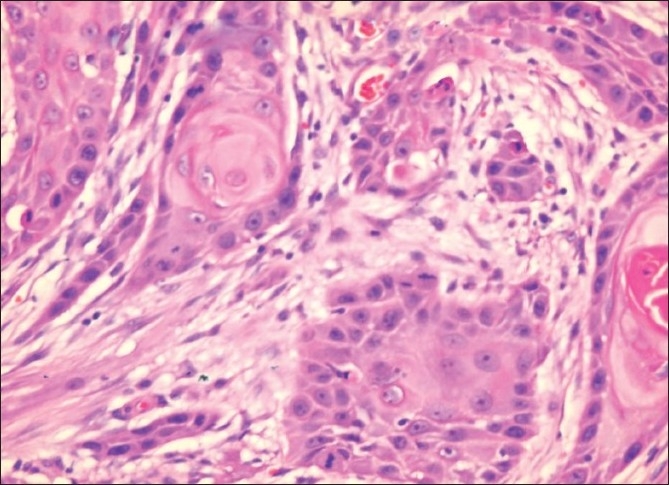

A 30-year-old gentleman received a live related kidney transplant in 2000. His intra- and postoperative course was uncomplicated. He was treated with azathioprine, cyclosporine, and prednisolone. Good renal function was achieved within a week after transplantation. Nine years later, the patient, entirely well in the interim, presented with a small non-healing ulcer on the left midlateral margin of the tongue. He was taken for a biopsy of that non-healing ulcer. A frozen section revealed a well-differentiated squamous cell carcinoma, for which he underwent left hemiglossectomy. Histopathology revealed a well-differentiated squamous cell carcinoma; the maximum depth of the invasion was 1.9 cm, with tumor-free excisional margins [Figure 1]. Lymphatic and blood vessel invasion were not seen. The patient apparently never used to smoke or consume alcohol and denied any history of chewing tobacco. He had no history of wearing dentures, nor were there any identifiable factors, which may have contributed to chronic irritation.

| Figure 1 Well-differentiated squamous cell carcinoma of the tongue